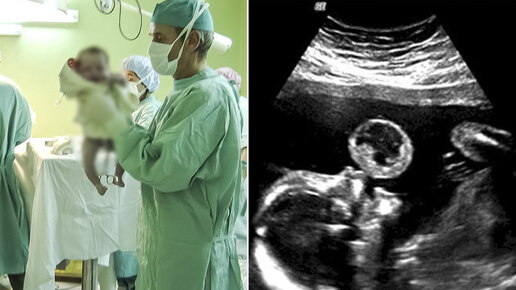

Мама видит, как ребенок «пускает пузыри» на УЗИ, доктор тут же предлагает ей сделать аборт...